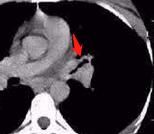

CT片上可以看到,右肺尖一个球形病灶,边界清晰,里面有多高斑点状的钙化,这个是典型的“结核球”。

观察他第一次的片子,在结核球的周围还有小斑片影和一些小结节(属于肺结核的卫星灶),本次已经基本吸收了,说明治疗有效。

我们从开篇第一张图中可以看出,小伙子的结核球属于孤立性病灶,伴有多发斑点状钙化,没有空洞,没有树芽征,也没有肺实变和磨玻璃密度影,气管壁没有增厚,说明不具备影像学的活动期表现。